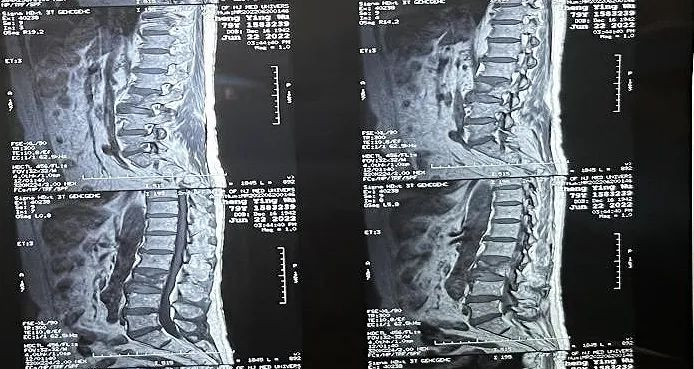

术中切口5毫米,在大平板C臂机的透视指引下,确定了进针的方向及进针的深度。经椎弓根向椎体置管,建立通道,插入骨扩张器(球囊)。球囊扩张恢复椎体高度,并在椎体内形成空腔,确定骨水泥的注入剂量,并注入骨水泥观察其扩散情况。

大平板C臂机临床图像